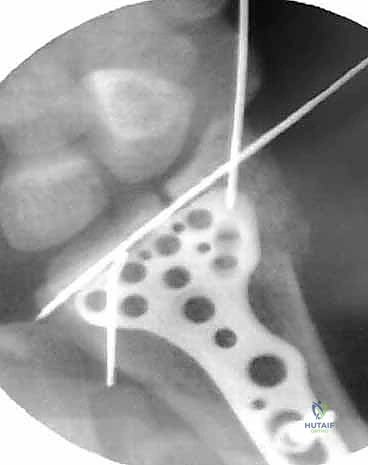

الخطوة الثانية: إدخال المنظار (Portals)

يقوم الدكتور هطيف بعمل 2 إلى 3 ثقوب دقيقة جداً (Portals) في ظهر الرسغ. يتم إدخال الكاميرا من ثقب، وأدوات العمل الجراحية الدقيقة من الثقوب الأخرى.

الخطوة الرابعة: رد الكسر تحت الرؤية المباشرة

باستخدام أدوات دقيقة، يتم تحريك القطع العظمية المكسورة وإعادتها إلى مكانها الطبيعي. يراقب الجراح العملية عبر شاشة المنظار ليتأكد من أن السطح المفصلي أصبح مستوياً تماماً بنسبة 100%.

الخطوة الخامسة: التثبيت الداخلي

بمجرد استعادة الشكل التشريحي، يتم تثبيت العظام. قد يتم استخدام أسلاك كيرشنر (K-wires)، مسامير دقيقة، أو شريحة معدنية داعمة (Volar Plate) توضع من خلال شق صغير منفصل لضمان ثبات الكسر التام. يتم أيضاً خياطة أي تمزق في الأربطة إن وجد.